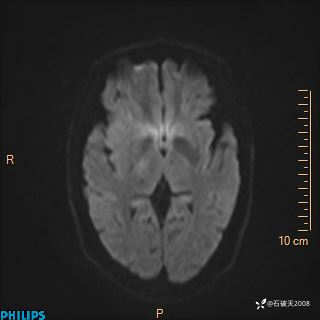

2024.2.21MR

DWI